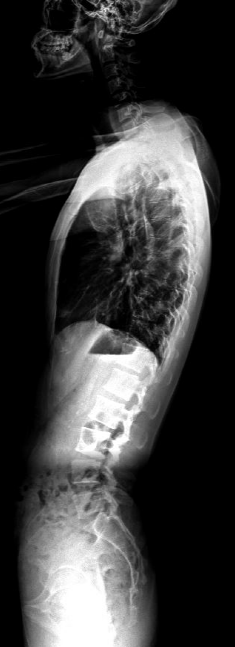

안면비대칭 교정, 거북목 교정 후 좁아서 기도가 확장되었습니다.

아래턱이 뒤로 밀리면 상대적으로 기도의 직경이 좁아집니다. 이런 경우 airway를 확보하기 위한 보상반응으로 목을 더 앞으로 빼는 자세를 취하게 되서 악순환은 반복됩니다. 안면비대칭 교정을 통해 거북목이 교정되면 아래턱이 앞으로 이동하면서 기도가 확보되면 목을 앞으로 빼지 않아도 airway가 충분히 확보되어 호흡이 편해집니다.